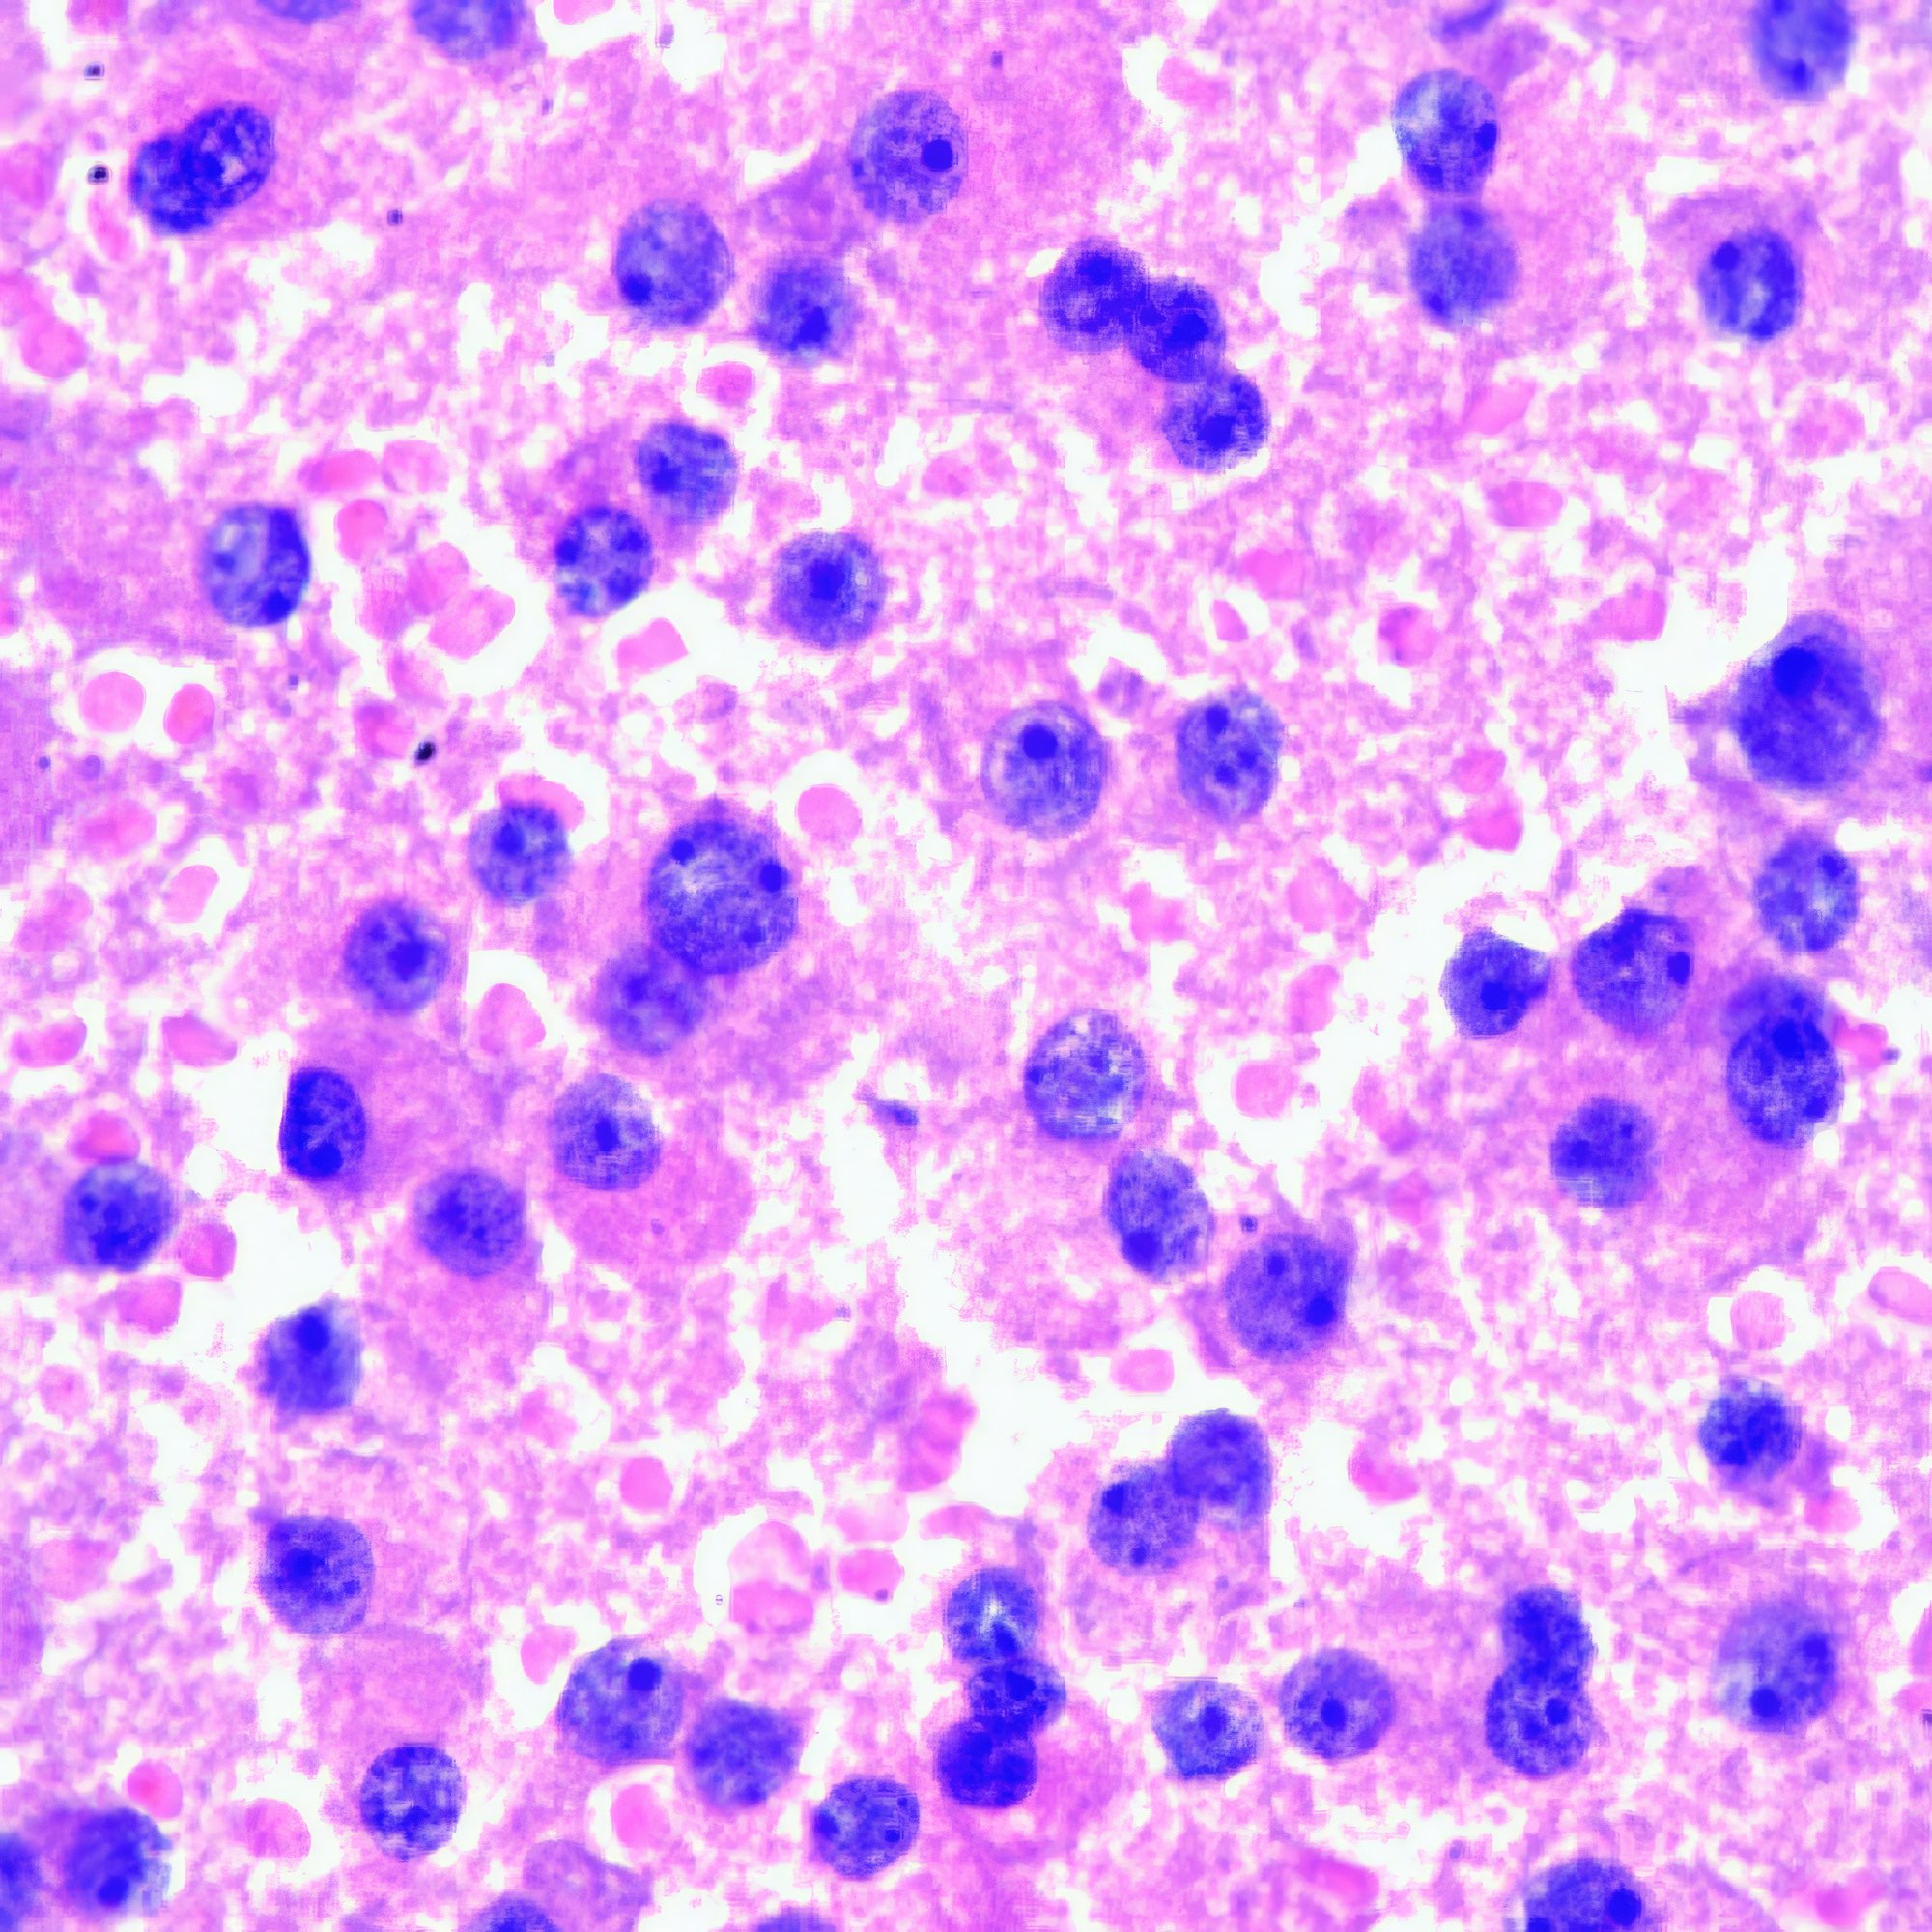

M, 55 Jahre, bemerkte seit 3 Monaten eine zunehmende inguinale Lymphknotenschwellung, der größte 3 x 4 cm messend, davon Feinnadelaspiration (FNA). Abbildung 1 bis 4: Verschiedene Areale des zytologischen Ausstrichs. Orig. 63x

Beschreibung

Die Bilder zeigen hochatypische Zellen. Deren überwiegend runde, teils auch ovalen Kerne variieren erheblich in ihrer Größe, sind deutlich grob strukturiert und enthalten meist ein oder mehrere prominente Nukleolen bzw. Chromozentren. Das Zytoplasma erscheint fragil. In jedem Bild finden sich auch Zellen mit pigmentbeladenem Zytoplasma. Der Ausstrichhintergrund enthält Blut und Zelldetritus, ebenfalls vermischt mit Pigmentkörnchen.

Kommentar

Der Patient beobachtete seit einem Jahr am Fuß eine pigmentierte Veränderung, die seit 3 Monaten auf 3 cm Durchmesser zunahm. Die prominente Atypie und die pigmenthaltigen Zellen sowie die ausgedehnte Metastasierung in die inguinalen Lymphknoten sind typisch für das Melanom. Eine Verwechslung des Melanin-Pigments mit Hämosiderin ist wegen der Zellatypie so gut wie ausgeschlossen. – Amelanotische Melanome zeigen oft eine weniger ausgeprägte Kernatypie und sind eher mit einem anderen Tumor zu verwechseln.